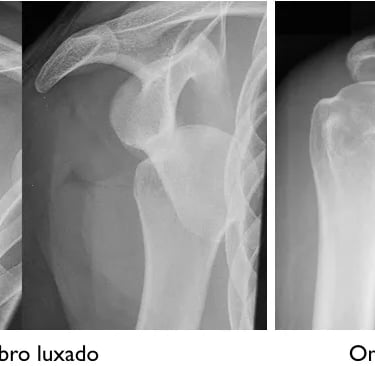

Luxação do Ombro

Luxação do ombro é a perda de contato entre a cabeça do úmero que perde o contato e a glenoide, a parte articular da escápula. O deslocamento causa geralmente as lesões de Bankart e Hill-Sachs. A lesão de Bankart é o destacamento dos do lábio, ou labrum, da glenoide. A função do lábio glenoidal é servir de ancoragem para os ligamentos e aumentar a estabilidade da articulação. Ela ocorre porque a cabeça do úmero tem um osso mais frágil do que o osso da glenoide.